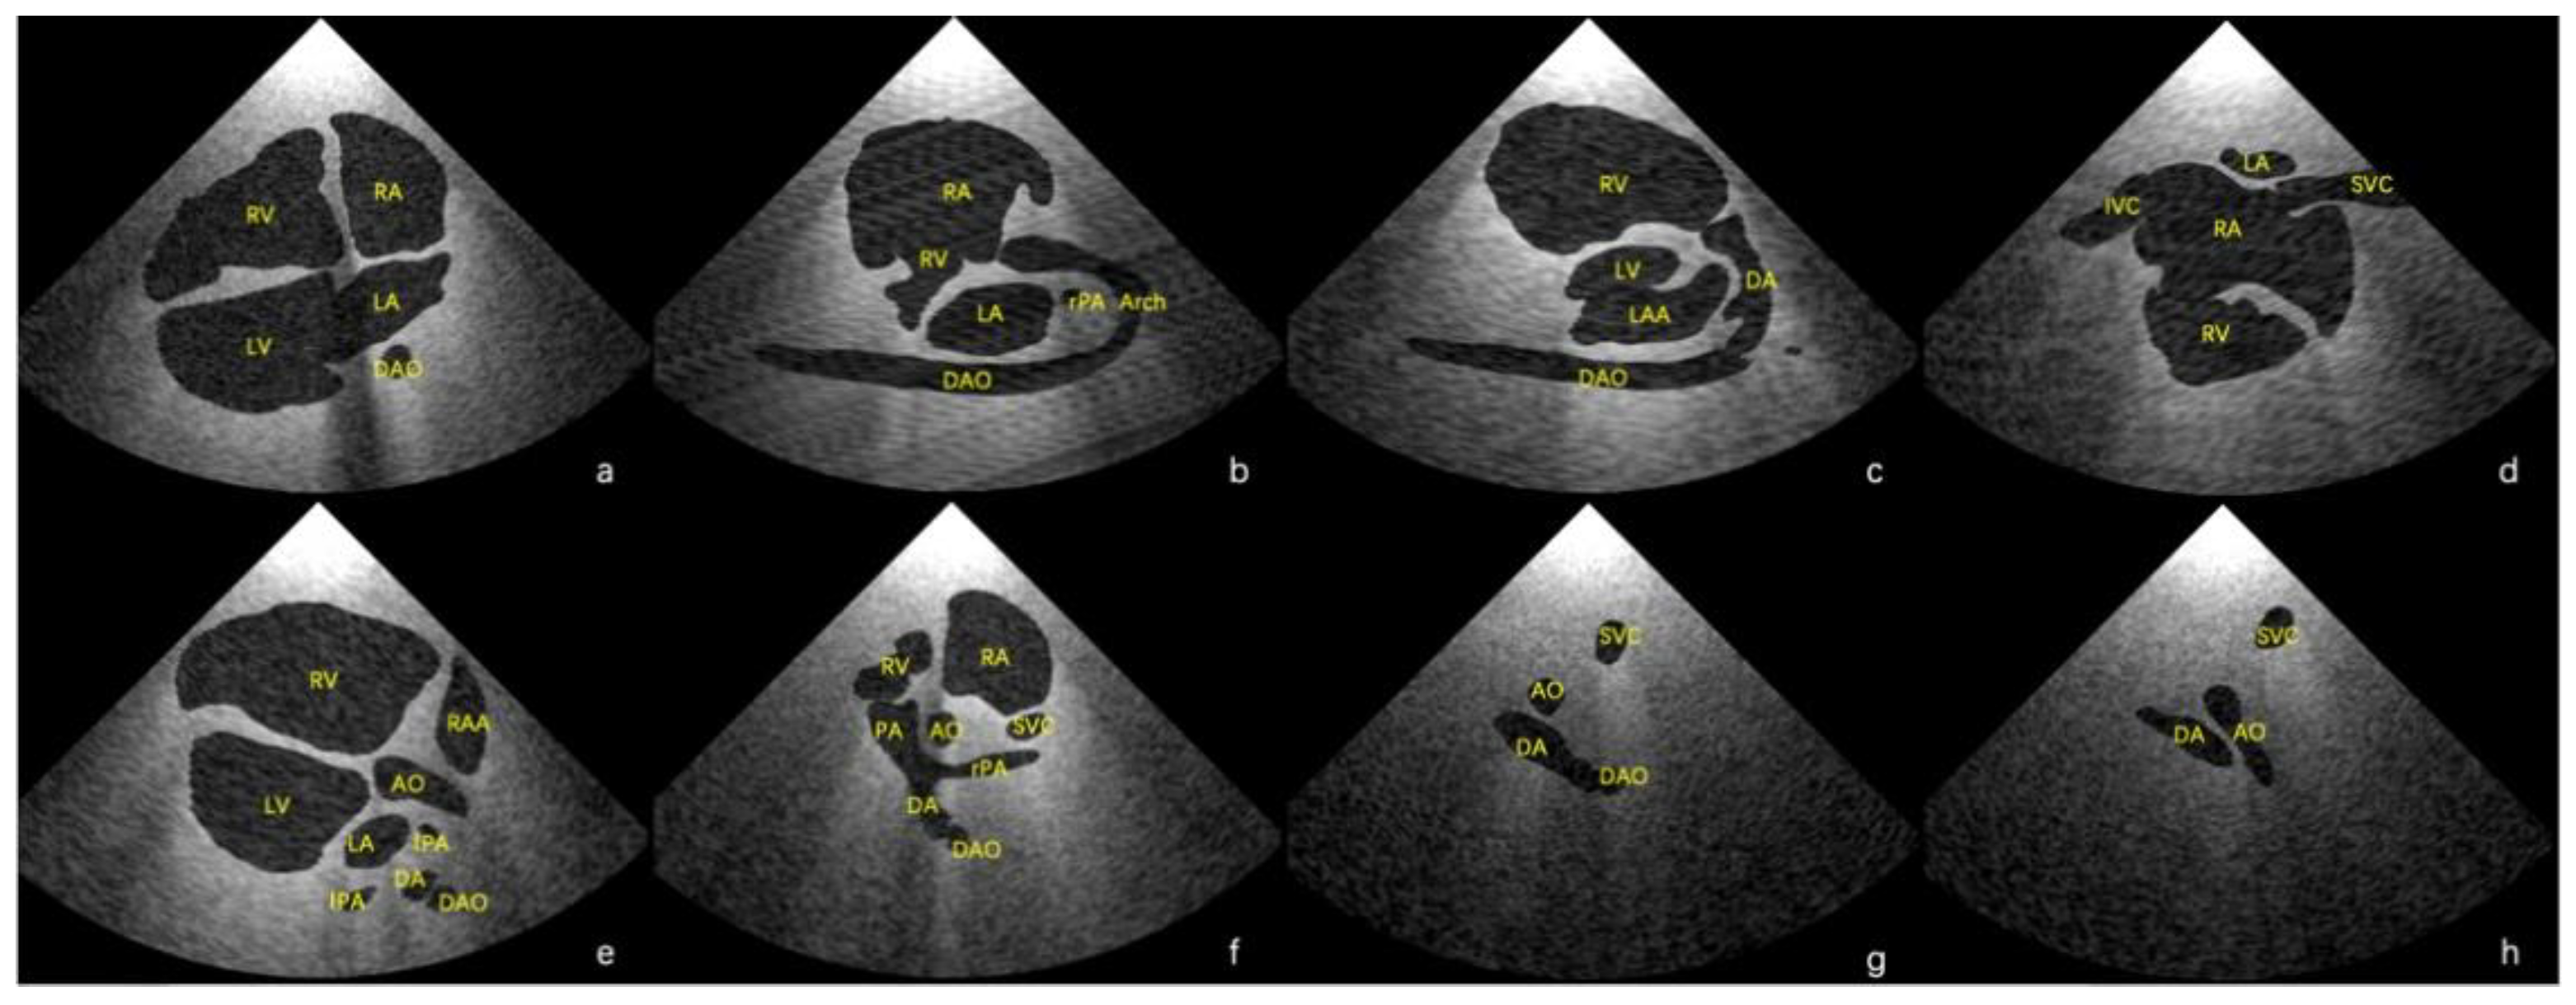

Using the final scenes, eight main standard views (four-chamber view, left ventricular outflow tract view, right ventricular outflow tract view, three-vessel view, three vessels and trachea, aortic arch view, ductal view, and bicaval view) [23,24] and additional views in which the lesion was adequately demonstrated could be obtained. Examples of standard views for the normal heart are shown in Figure 3, and example views with diagnostic values for the two abnormal hearts are shown in Figure 4. As shown in Figure 4a, there is an abnormal vessel between the DA and the aortic arch in the three vessels and the trachea view. In Figure 4b, the probe moves toward the cephalic side of the fetus from the three-vessel trachea view to show a cross-section of the double aortic arches. In Figure 4c, the double aortic arch connects the descending AO at the coronal level. In Figure 4d, the RV is significantly smaller than the LV in the four-chamber view. In Figure 4e, there is a channel between the left and right ventricles (indicated by the arrow), and the AO arises from the RV. In Figure 4f, the initial part of the PA is not connected to the ventricle (indicated by the arrow).

Figure 3. Eight main standard virtual views of echocardiography in Case 1. (a) Four-chamber view, (b) aortic arch view, (c) ductal view, (d) bicaval view, (e) left ventricular outflow tract view, (f) right ventricular outflow tract view, (g) three-vessel view, and (h) three vessels and trachea view. AO—aorta; Arch—aortic arch; DA—ductus arteriosus; DAO—descending aorta; IVC—inferior vena cava; LAA—left atrial appendage; LV—left ventricle; PA—pulmonary artery; RA—right atrium; RAA—right atrial appendage; RV—right ventricle; SVC—superior vena cava.